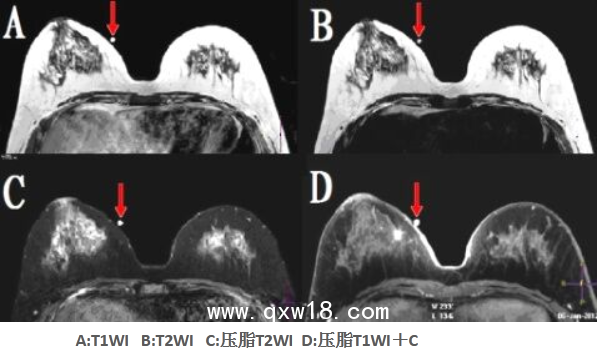

該型號(hào)定位貼尤其適用于神經(jīng)系統(tǒng)定向穿刺活檢、機(jī)器人導(dǎo)航手術(shù)等,比國(guó)外同類產(chǎn)品優(yōu)點(diǎn)突出:①球和座可組可分;配準(zhǔn)注冊(cè)孔為陽性標(biāo)記。②座受壓不變形。③在CT、T1WI、T2WI、FLAIR(壓水像)、STIR(壓脂像)等多個(gè)掃描序列上均成像明顯。④經(jīng)在北京航空航天大學(xué)研制的立體定向神經(jīng)導(dǎo)航機(jī)器人上驗(yàn)證,標(biāo)記定位的精度高于國(guó)外產(chǎn)品。